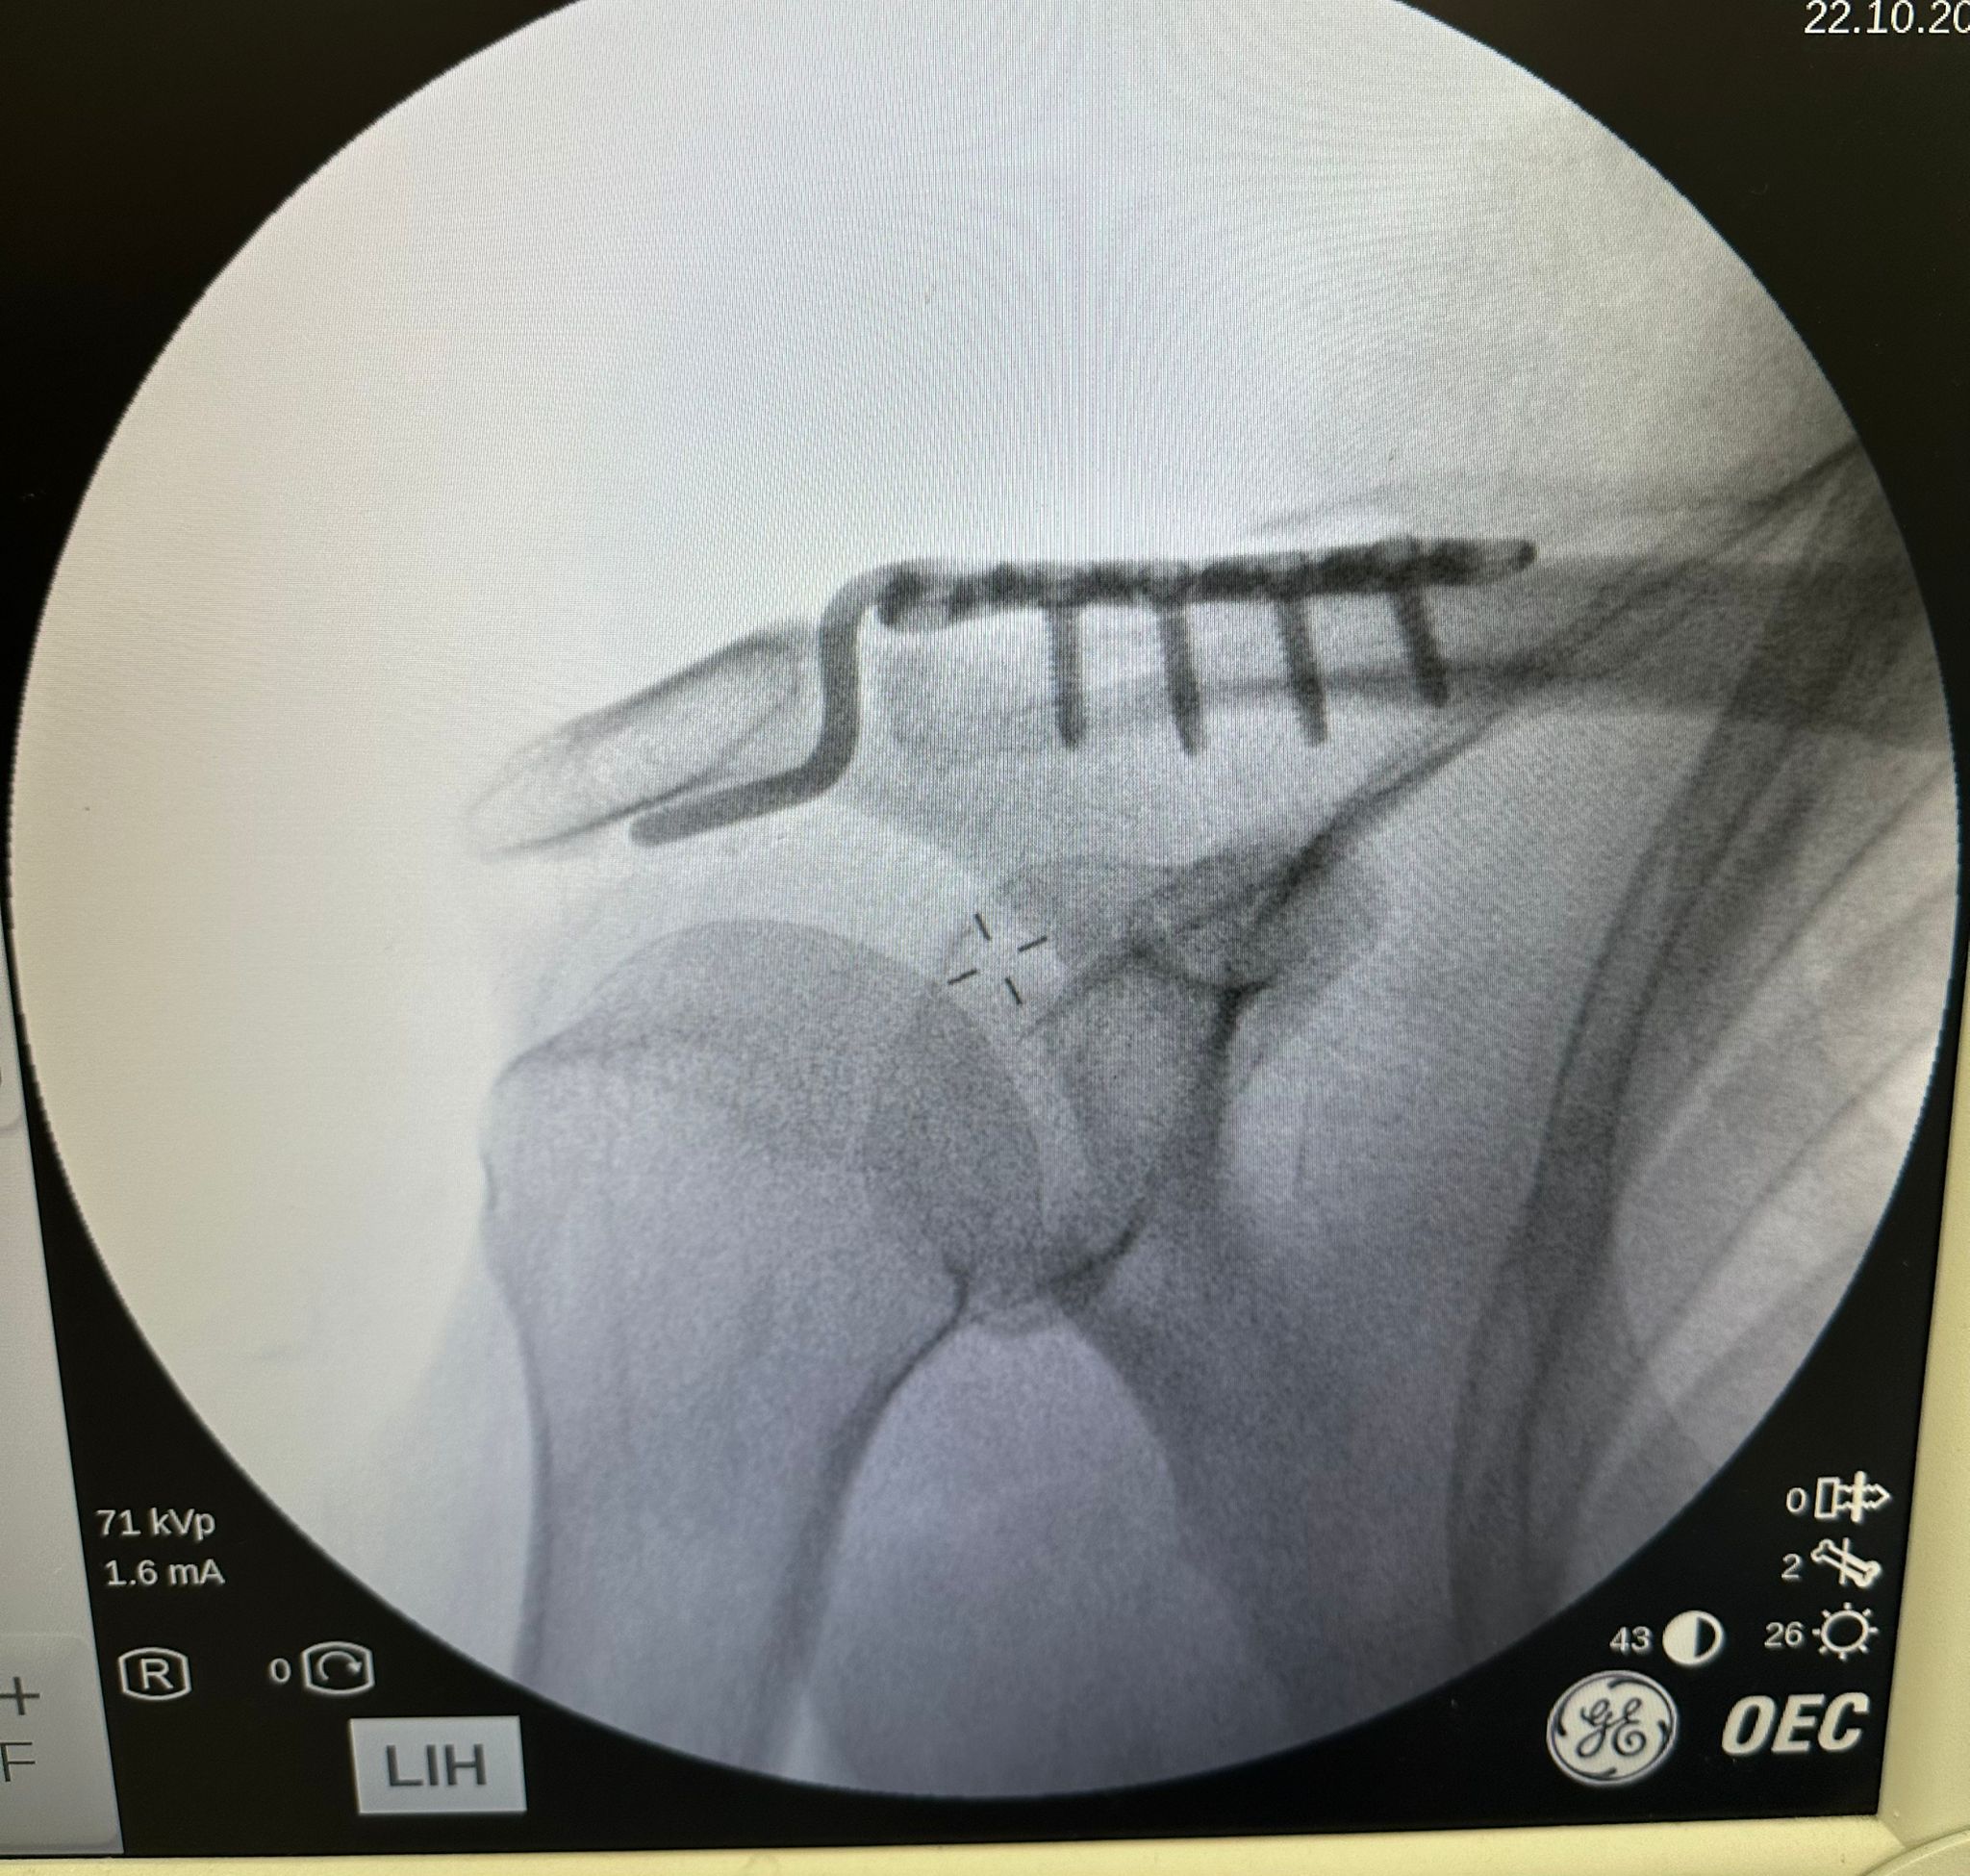

Ortopedi ve Travmatoloji Uzmanı Dr. Mehmet Yavuz Başer’in gerçekleştirdiği ameliyatta, Rençber’in omzuna kemik yapısıyla tam uyumlu, nadir kullanılan özel bir plak yerleştirildi.

Ameliyatın çok başarılı geçtiğini belirten Dr. Mehmet Yavuz Başer, “Genelde gençlere ameliyat önerilirken bu hastamıza yaşından dolayı bazı sıkıntılar olduğu söylenmiş. Biz kendisiyle konuştuk ve aktif birisi olduğu için ameliyat kararını daha uygun gördük. Ameliyatımız çok şükür güzel geçti. Nadir kullanılan bir plaktan kullandık, o da hastamıza tam olarak uydu” dedi.